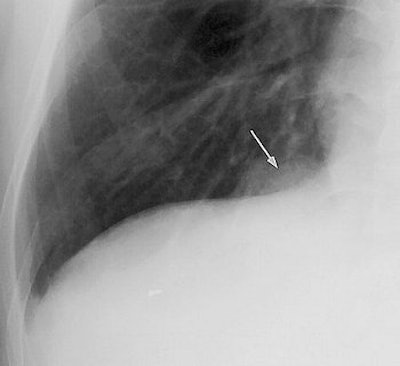

![]() |

| Image C. Transverse contrast-enhanced chest CT scan (5-mm collimation), obtained through the right half of the diaphragm at the same time as image B, shows that the mass in image B results from an inhomogeneously enhancing pulmonary lesion (arrow) abutting the pleura. The mass disappeared nine months later with use of antituberculous medication. Figures 2a, b, c, Choi, YW, Jeon SC, Seo HS, et al, "Tuberculous pleural effusion: New pulmonary lesions during treatment," (Radiology 2002; 224: 493-502). |